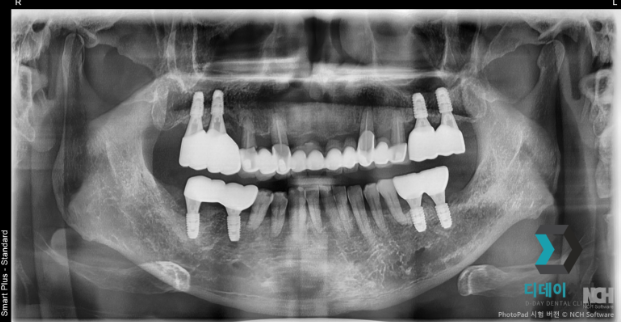

어금니 임플란트 치료를 위해 내원하신 환자분입니다.

오른쪽 위 어금니 발치한 상태로 내원하셨고

상악동 함기화로 인해 치조골이 부족한 상태였기때문에

상악동 거상술을 같이 진행했습니다.

2024-07-08